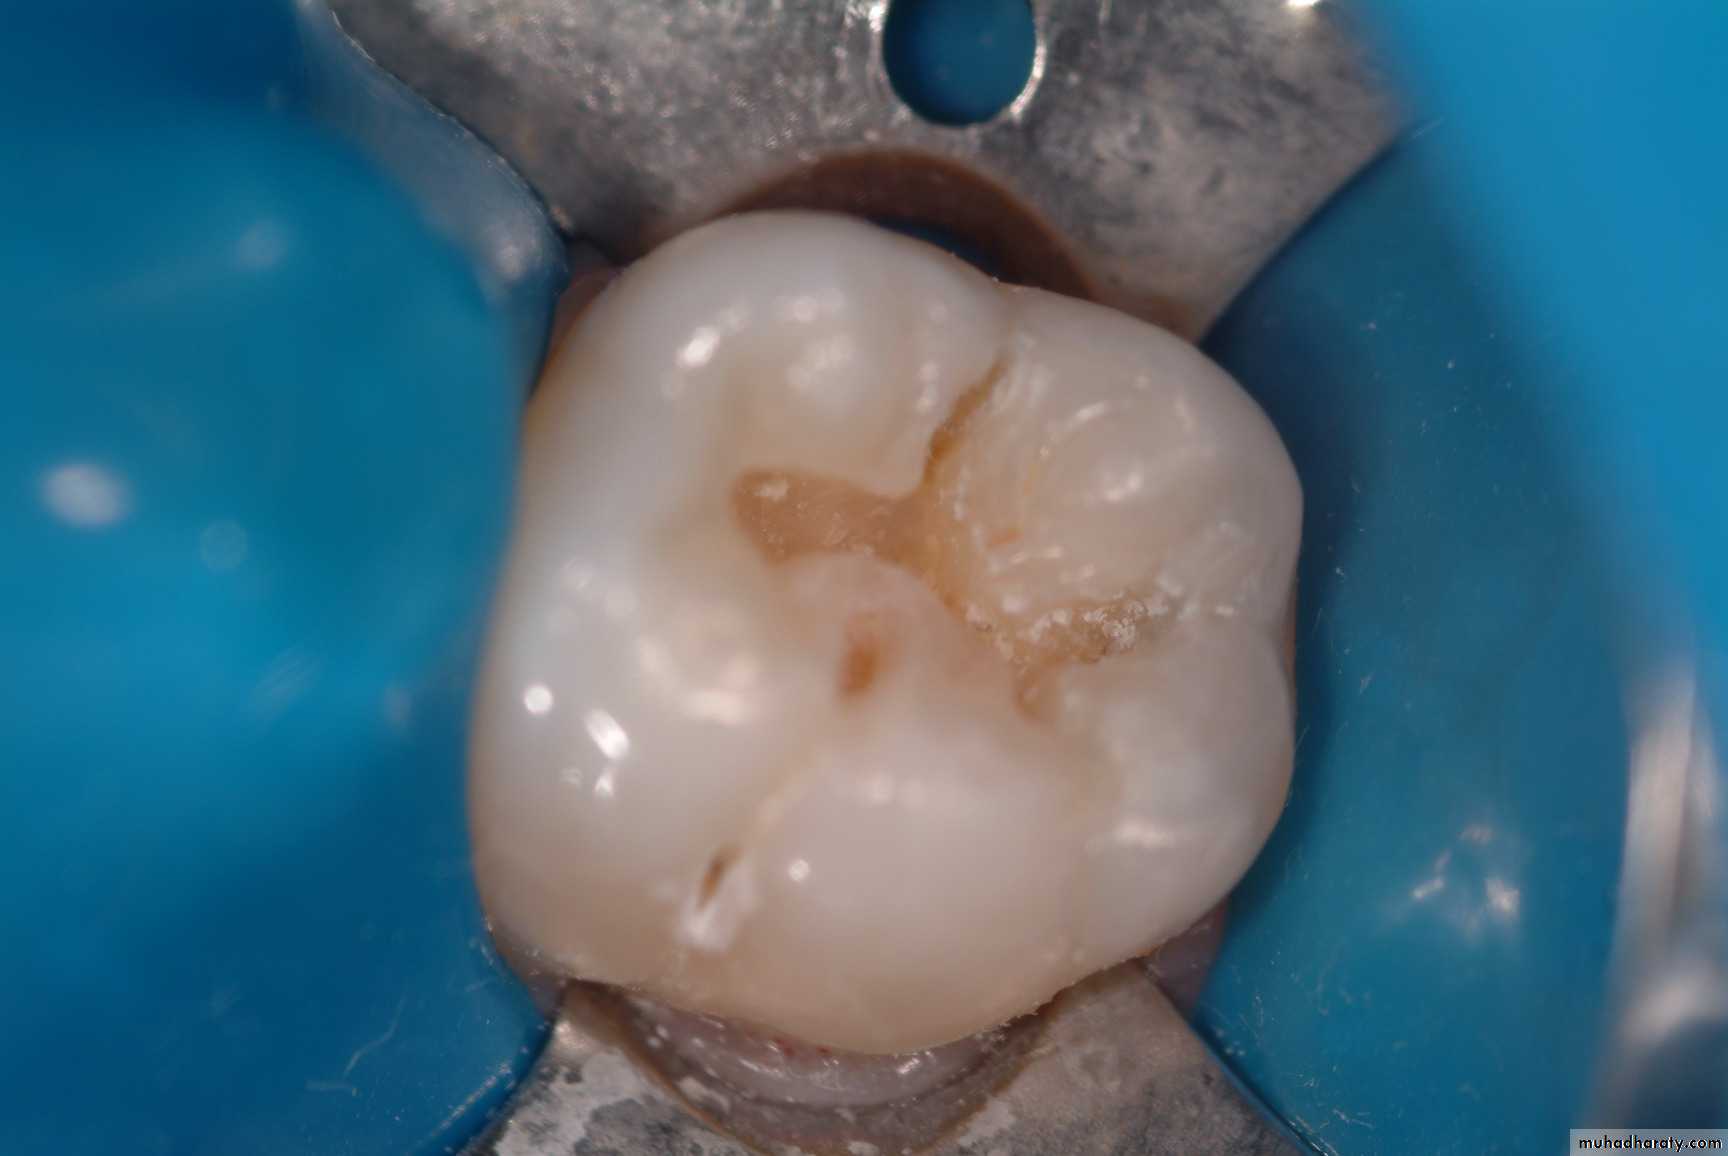

Diagnosis Of Dental Caries

Earliest caries detection, traditionally by use of mirror and light, as well as bitewing radiographs, can now be aided by new innovations in dental magnification and imaging, laser fluorescence and quantitative light-induced fluorescence.

Higher intensity in caries region

severity of tooth decay

Effect on carious lesions